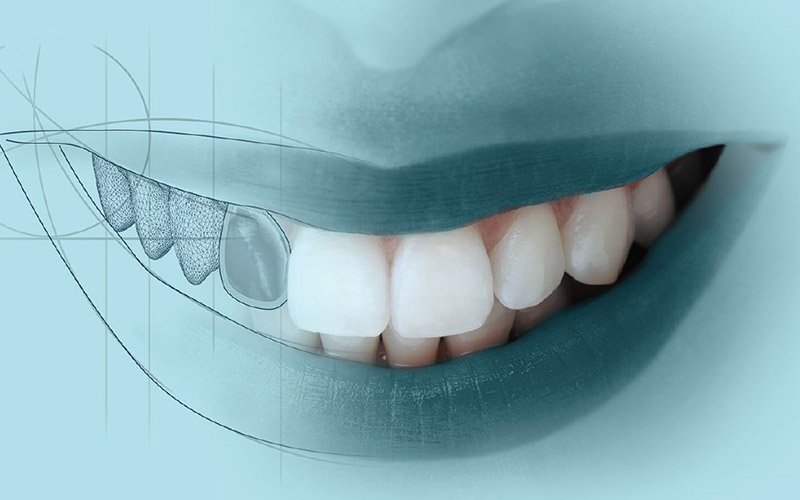

PROTESI DENTARIE

Protesi dentarie oggi non sono solo una soluzione funzionale per i denti persi. In stomatologia contemporanea protesi coprono due ruoli: funzionale ed estetico. Oggi si chiedono sempre di più corone non metalliche (in zirconio) e ponti. I pazienti vedono queste lavorazioni come sostituzioni perfette per i denti persi.